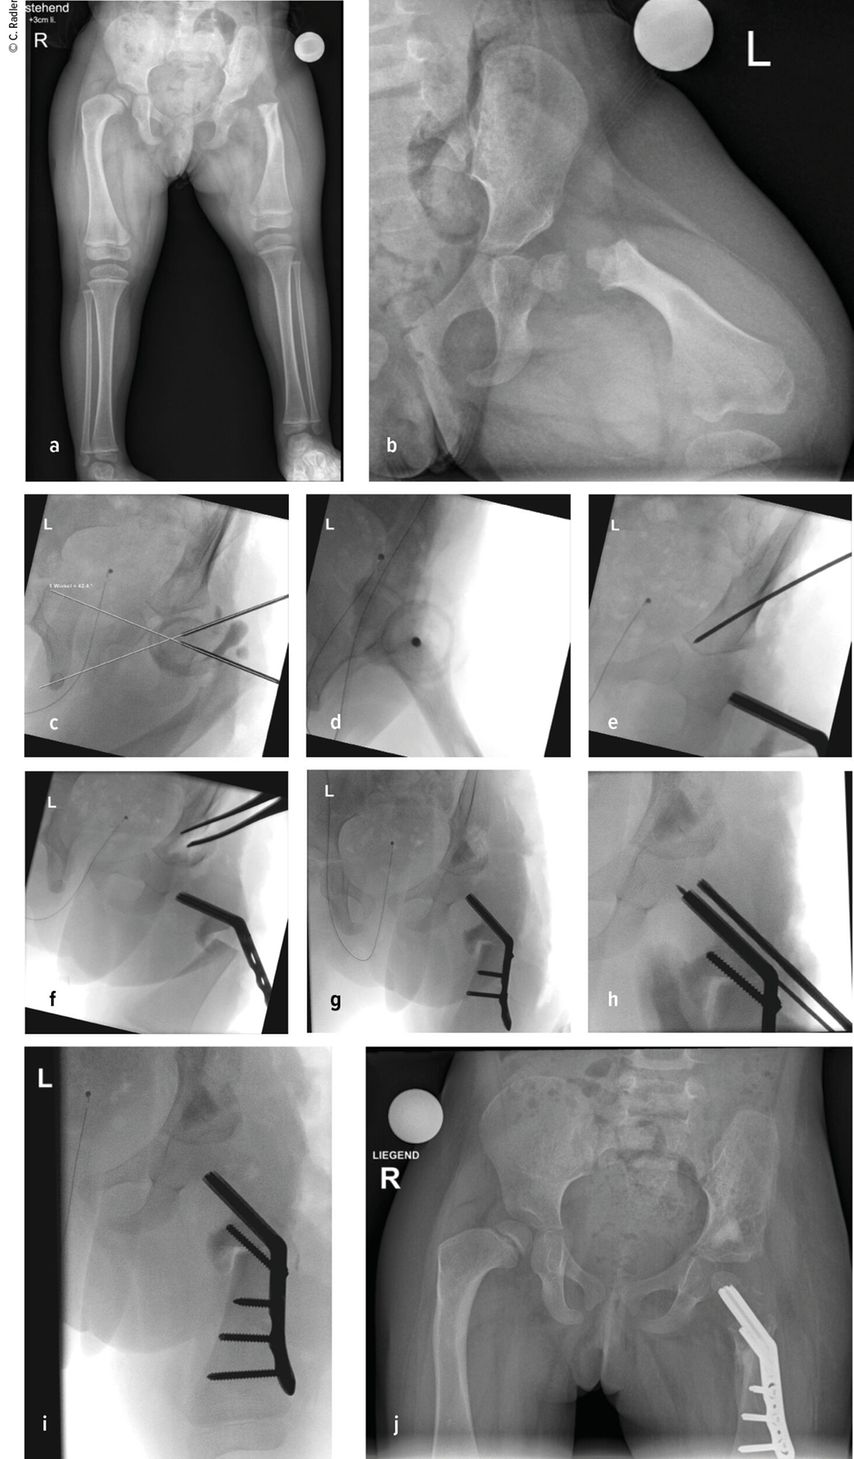

Der Typ 1B ist durch eine verzögerte Ossifikation/Pseudoarthrose subtrochantär oder im Schenkelhalsbereich charakterisiert, wobei auch ein kombinierter Typ mit Schenkelhals und subtrochantär verzögerter Ossifikation vorliegen kann. Klinisch imponiert neben der massiven Verkürzung die Außenrotations- und Beugekontraktur. In diesen Fällen ist eine komplexe Rekonstruktion, bestehend aus mehreren Schritten, erforderlich, die als Super-Hip-Operation subsumiert wird (Abb. 3).

Hierbei erfolgt der Zugang über einen breiten, lateralen Schnitt von der Mitte der Beckenschaufel über den Trochanterbereich oder auch den fallweise sichtbaren Haut-Dimple über die Mitte des Oberschenkels bis zum Knie bzw. bis zur Tuberositas tibiae, wenn eine gleichzeitige Stabilisierung des Kniegelenks erforderlich ist. Es wird die Faszie im Bereich des Intervalls zwischen Tensor fascia lata und Sartorius inzidiert und hier schließlich die proximale ventrale Grenze zum Absetzen der Faszien definiert. Distal erfolgt die Inzision etwas lateral der Patella. Diese beiden Inzisionen werden nun verbunden, dorsal wird die Faszie distal etwas posterior des intermuskulären Septums gespalten. Die Fascia lata kann entweder zur Stabilisierung des Kniegelenkes verwendet werden oder wird am Ende der Operation reseziert, um bei späteren Verlängerungen diese nicht zu behindern. Im nächsten Schritt erfolgt der Zugang über die Tensor-Lücke, wobei hier die Rectus-Sehne durchtrennt wird, was bereits einen Teil der Beugekontraktur korrigiert. Dies muss mit großer Vorsicht geschehen, da hier besonders bei schweren Formen des CFD der Femoralis-Nerv lateraler als üblich und damit näher am Rectus liegt. Im nächsten Schritt wird die Psoas-Sehne auf der Unterseite des Iliopsoas mit einer Klemme herausluxiert und ebenfalls durchtrennt. Ein weiterer wichtiger Faktor, besonders in Bezug auf die Abduktion und Außenrotation, ist der Piriformis, auch diese Sehne muss durchtrennt werden. Der Ischiadicus-Nerv ist hier sehr nahe und kann dabei oft gut identifiziert beziehungsweise in schweren Fällen auch neurolysiert werden.

Es wird dann auf die Beckenschaufel zugegangen und hier die Apophyse gesplittet und abgelöst. Dieser sogenannte Abductor-Slide entspannt weiter die kontrakte Muskulatur, da vor der Rückvernähung der Apophyse ein Teil des Beckenkamms abgetragen wird. Erst jetzt wird an das Femur herangegangen. Da besonders bei schweren Fällen an der Hüfte nur der Hüftkopfkern sichtbar ist, muss eine Arthrografie durchgeführt werden, um ein Setzen der Bohrdrähte für die Platte zu ermöglichen. Ein erster Bohrdraht wird vom palpierten Trochanter major in das Zentrum des Hüftkopfkernes gesetzt. Ein zweiter Bohrdraht wird etwa in 45° zu diesem wiederum in das Zentrum des Hüftkopfkerns gesetzt. Die Lage des Bohrdrahtes wird im Bildwandler überprüft und kann im seitlichen Strahlengang durch die Überlappung von Hüftkopfkern, Schenkelhals und Kapsel bestätigt werden. Dann kann die Platte schließlich über diesen eingebracht werden. Die Osteotomie des Femurs erfolgt dann in 90° zur liegenden Platte und wiederum in 90° zu diesem Schnitt. Medial muss auch das Periost durchtrennt und releast werden. Nun zeigt sich bereits, wie sehr das Femur verkürzt werden muss, um spannungsfreie Korrekturen zu ermöglichen. Die Platte wird jedoch erst nach der Acetabuloplastik fixiert, um Länge und Rotation korrekt einstellen zu können. Die Acetabuloplastik wurde klassisch als modifizierte Dega-Osteotomie durchgeführt, wobei sich über eine unikortikale Iliumosteotomie („Paley unicortical ilium osteotomy“) eine bessere Überdachung erreichen lässt.

Hierzu wird das Periost des Iliums bis zur Incisura ischiadica und bis knapp oberhalb des Acetabulums abgelöst. Medial wird das Periost im Bereich des Os pubis eingeschnitten, um eine bessere Mobilität des Fragmentes zu erzielen. Es wird dann von knapp oberhalb der Kapsel entlang der Incisura etwa 2–3cm nach proximal gemeißelt. Dann wird ein Bohrdraht gesetzt, der medial auf die Y-Fuge zielt. Entlang des Bohrdrahts wird die Osteotomie schließlich durchgeführt, wobei nur ganz ventral das Ileum medial durchtrennt wird, und hier in Richtung Pubis, wodurch wiederum kaum die mediale Kortikalis überschritten wird. Es kann nun die Osteotomieöffnung entsprechend aufgespreizt und ein Knochenstück aus der Femurverkürzung eingebracht werden. Entsprechend der Überlappung des distalen Femursegmentes in korrigierter Position werden schließlich auch die Resektionhöhe und das Ausmaß der Resektion des Femurs definiert. Nach entsprechender Verkürzung wird über Fixation der Platte schließlich auch die Rotation mit etwa 10° Antetorsion festgesetzt.

Typ 1B2 und 1B3